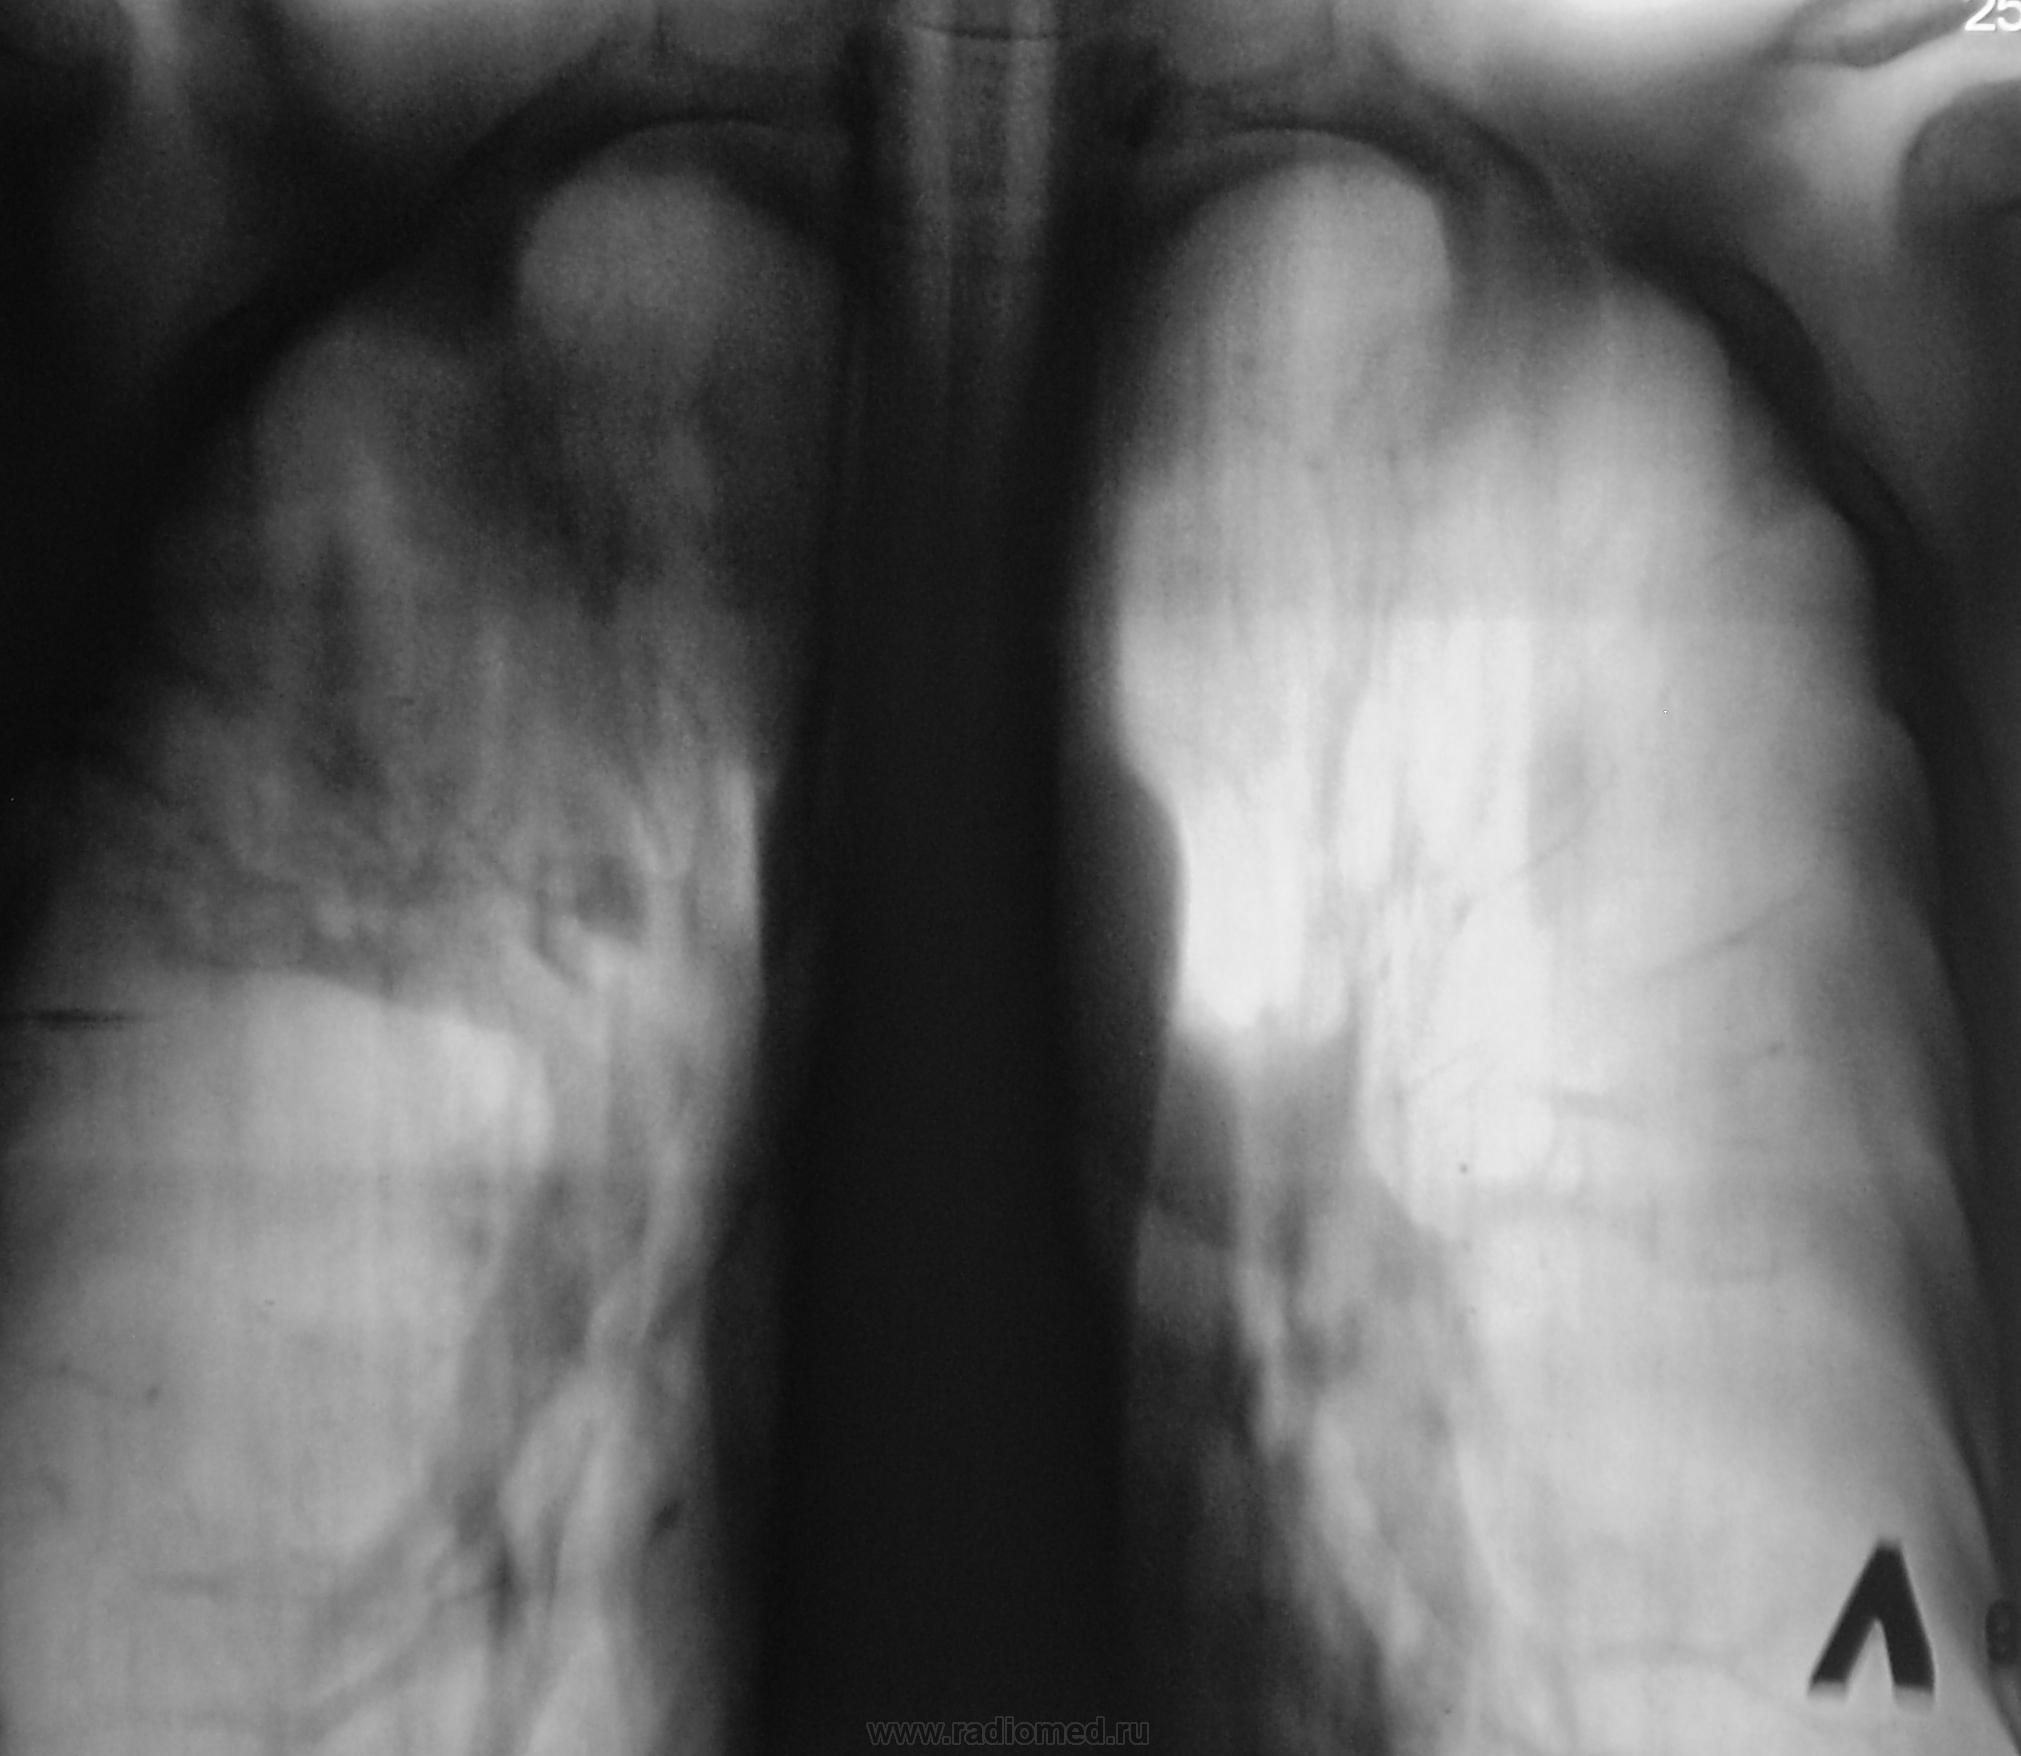

Взят на контроль, дообследован. Какие мнения будут уважаемые коллеги?